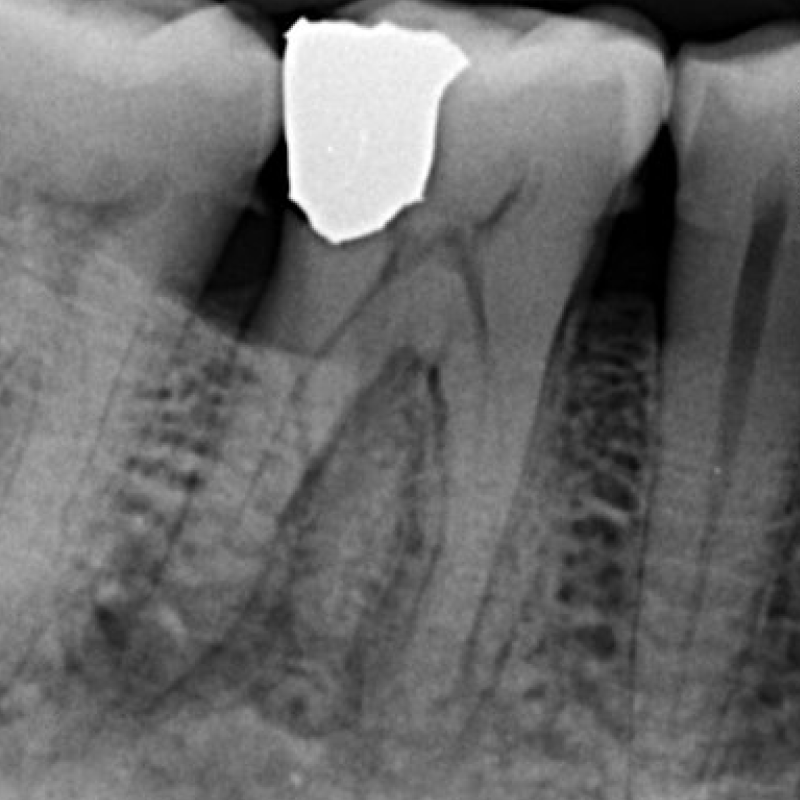

Before

After

Radix Entomolaris

3 Rooted Premolar

Re-RCT

Curved canals

Mulbery Molar

Molar with 6 canals